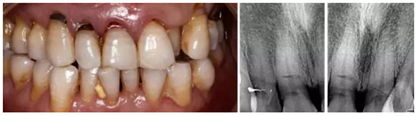

1.臨床病例:患者,男,年齡73歲,不慎摔倒至右上頜側(cè)切牙、左右上頜中切牙外傷根折,X線檢查:12、11、21折裂線達(dá)牙頸部以下。CBCT檢查:12、11、21折裂線呈水平狀,達(dá)牙頸部以下。

2.診斷:左上頜側(cè)切牙、左右上頜中切牙根折

(1)拔牙后PRF復(fù)合GBR技術(shù)行位點(diǎn)保存